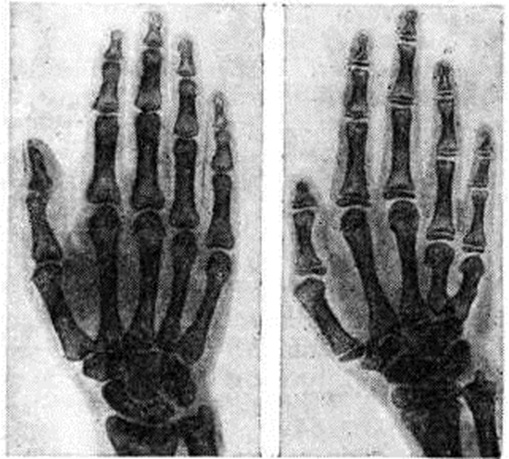

Рис

Рентгенограмма кисти здорового человека (слева) и больного гипогонадизмом (справа); укорочение IV и V пястных костей.

У больных первичным Гипогонадизм, связанным с генетической патологией (смотри Тернера синдром), встречаются аномалии развития скелета (напр., укорочение фаланг IV—V пальцев кистей и стоп, укорочение IV и V пястных костей) — положительный метакарпальный синдром (рисунок), деформация Маделунга, врождённые клиновидные позвонки, веерообразное слияние рёбер, деформации грудины и медиальных мыщелков большеберцовых костей.